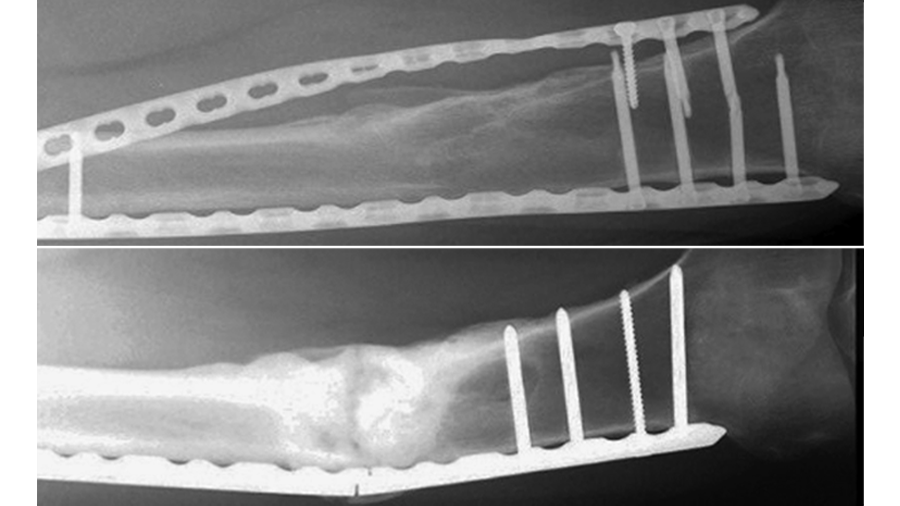

Recently, anterior variable angle locking plates have been developed for treatment of both simple and comminuted patella fractures (Fig 1).

Sixteen pairs of human anatomical knee specimens were used to simulate either two-part transverse simple AO/OTA 34-C1 or five-part complex AO/OTA 34-C3 patella fractures by means of osteotomies, with each fracture model being created in eight pairs. The complex fracture pattern was characterized with a medial and a lateral proximal fragment, together with an inferomedial, an inferolateral, and an inferior fragment mimicking comminution around the distal patellar pole. The specimens with simple fractures were pairwise assigned for fixation with either tension band wiring through two parallel cannulated screws, or an anterior variable angle locking core plate. The knees with complex fractures were pairwise treated with either tension band wiring through two parallel cannulated screws plus circumferential cerclage wiring, or an anterior variable angle locking three-hole plate. Each specimen was tested over 5000 cycles by pulling on the quadriceps tendon, simulating active knee extension and passive knee flexion within the range from 90° flexion to full knee extension. Interfragmentary movements were captured by means of motion tracking (Fig 2).